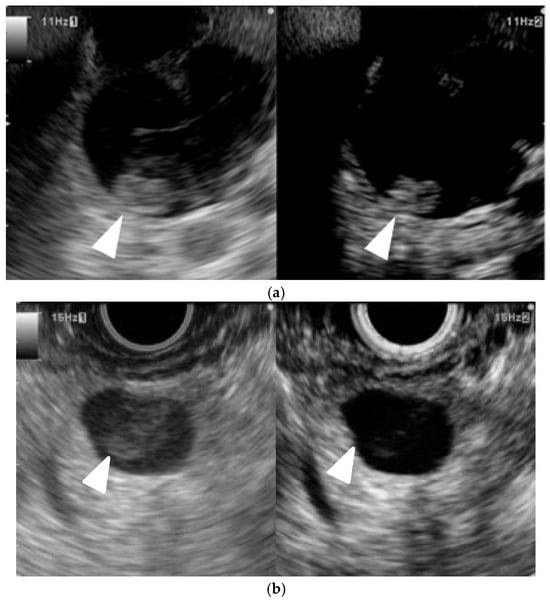

According to guidelines for IPMN [41], the presence or absence of mural nodules is a key factor in the decision to perform surgery; accurate evaluation can be problematic. Sometimes, they struggle to differentiate mural nodules from mucous clots. CH-EUS can be useful for assessing vascularity in mural lesions, which is helpful for differential diagnosis of mural lesions (Figure 6). The sensitivity, specificity, positive predictive value, negative predictive value, and accuracy of CH-EUS for detecting mural nodules is 100%, 80%, 92%, 100%, and 94%, respectively, whereas those for CT are 58%, 100%, 100%, 50%, and 71%, respectively [42]. With respect to the differential diagnosis of benign and malignant IPMNs, a meta-analysis of eight studies involving 320 patients with CH-EUS revealed that the pooled sensitivity, specificity, and diagnostic accuracy for the diagnosis of high-grade dysplasia (HGD) or invasive carcinoma (IC) within mural nodules is 97.0%, 90.4%, and 95.6%, respectively, when mural lesion with vascularity was defined as the malignancy [43]. Therefore, guidelines recommend CH-EUS in cases of IPMN with suspicion of HGD/IC if the clinical setting is available for the assessment of high-risk stigmata (HRS) and worrisome features (WFs) [41].

Figure 6. Typical contrast-enhanced harmonic EUS (CH-EUS) images of a mural lesion in IPMN. (a) Mural nodule. B mode EUS (left) shows an isoechoic mural lesion (arrowhead) in a cyst. CH-EUS (right) shows a mural lesion with vascularity (arrowhead). (b) Mucous clot. B mode EUS (left) shows an isoechoic mural lesion (arrowhead) in a cyst. CH-EUS (right) shows a mural lesion without vascularity (arrowhead).